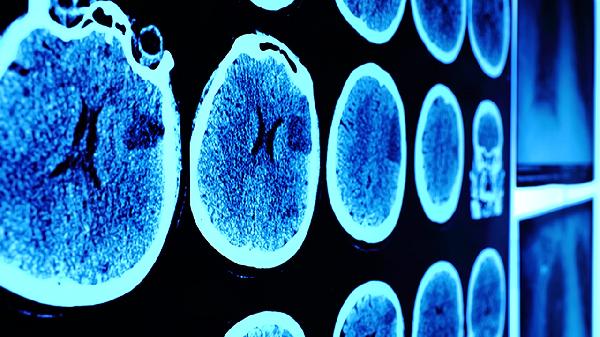

轻微脑震荡通常表现为短暂意识丧失、头痛、头晕等症状,多数无须特殊治疗,但需密切观察。轻微脑震荡可能与头部外伤、运动撞击等因素有关,通常表现为恶心、短暂记忆障碍、注意力不集中、睡眠紊乱、情绪波动等症状。若症状持续或加重,建议及时就医。

轻微脑震荡后可能出现数秒至数分钟的意识模糊或丧失,通常能自行恢复。此时应让患者平卧,保持呼吸道通畅,避免移动头部。若意识丧失时间超过10分钟或反复发作,需立即就医排除颅内损伤。

多数患者会出现持续性头痛或眩晕感,可能与脑组织轻微水肿有关。建议静卧休息,避免强光噪音刺激。可遵医嘱使用布洛芬缓释胶囊、对乙酰氨基酚片等镇痛药物,但禁止自行服用阿司匹林肠溶片等可能增加出血风险的药物。

部分患者对受伤过程出现逆行性遗忘,或短期内出现顺行性记忆困难。这种记忆缺损通常会在24-48小时内逐渐恢复。家属应协助记录关键事件,避免让患者单独处理重要事务。